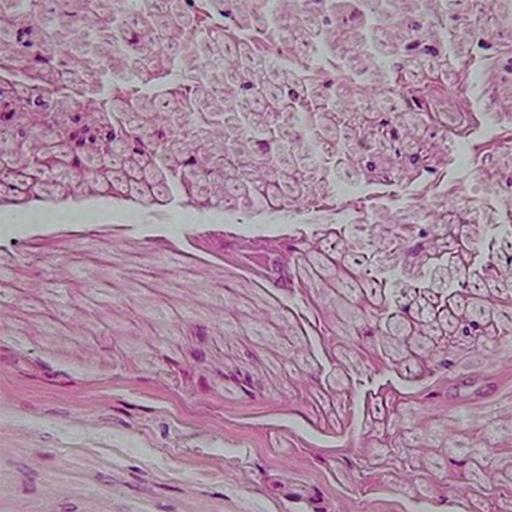

“Tissues” is the 6th chapter in the NCERT science textbook of standard IX. All living organisms are made of cells. Unicellular organisms have a single cell whereas multicellular organisms have millions of cells. In unicellular organisms, a single cell performs all basic functions. In multicellular organisms, a particular function is carried out by a cluster of cells at a specific place in the body. Cluster of cells that are arranged and designed to give the highest possible efficiency of function is called tissue. Are you interested in understanding more about animal tissues? View this PPT to learn this topic through vibrant and colourful slides. To cover the whole chapter, download this PPT along with the second part of ‘Tissue’ and score excellent marks in exams.